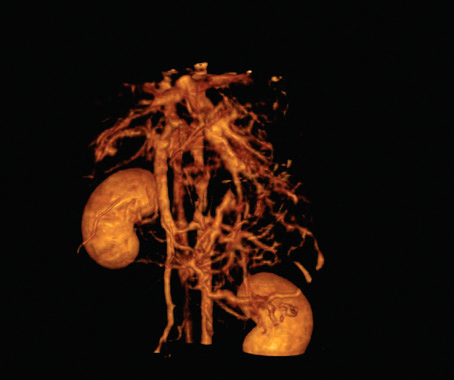

APLICAÇÕES CLINICAS